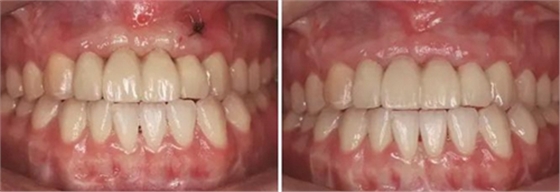

圖29 根管治療后的13行纖維樁修復(fù) 圖30 個(gè)性化轉(zhuǎn)移桿開窗取模

圖31 Index引導(dǎo)下試戴個(gè)性化氧化鋯基臺(tái) 圖32 個(gè)性化氧化鋯基臺(tái)于口內(nèi)就位

圖33 氧化鋯基底于口內(nèi)就位咬合正面觀 圖34 袖口正面觀

圖35 預(yù)粘接 圖36 戴入全瓷修復(fù)體正面觀

圖37 戴入全瓷修復(fù)體局部舌側(cè)觀 圖38 永久修復(fù)后微笑

圖39 永久修復(fù)后大笑